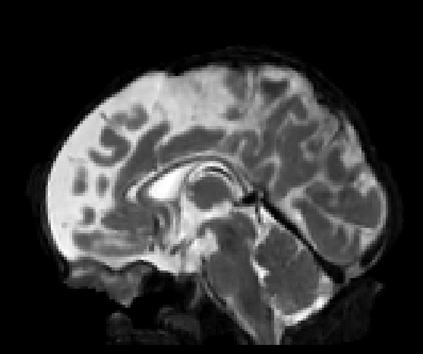

Real-world settings often do not allow acquisition of high-resolution volumetric images for accurate morphological assessment and diagnostic. In clinical practice it is frequently common to acquire only sparse data (e.g. individual slices) for initial diagnostic decision making. Thereby, physicians rely on their prior knowledge (or mental maps) of the human anatomy to extrapolate the underlying 3D information. Accurate mental maps require years of anatomy training, which in the first instance relies on normative learning, i.e. excluding pathology. In this paper, we leverage Bayesian Deep Learning and environment mapping to generate full volumetric anatomy representations from none to a small, sparse set of slices. We evaluate proof of concept implementations based on Generative Query Networks (GQN) and Conditional BRUNO using abdominal CT and brain MRI as well as in a clinical application involving sparse, motion-corrupted MR acquisition for fetal imaging. Our approach allows to reconstruct 3D volumes from 1 to 4 tomographic slices, with a SSIM of 0.7+ and cross-correlation of 0.8+ compared to the 3D ground truth.

翻译:现实世界环境往往不允许获取高分辨率的体积成像,以进行准确的形态评估和诊断;在临床实践中,通常常见的做法是只获得稀少的数据(如个别切片),以进行初步诊断决策;因此,医生依靠其人类解剖学的先前知识(或精神图)来推断基本的3D信息;准确的精神图需要多年的解剖培训,而这种培训首先依靠的是规范学习,即排除病理学;在本文中,我们利用贝耶斯深深层和环境绘图,从零到小、稀少的切片,产生完整的体积解剖面表(如个别切片);我们评估概念实施的证据,其基础是基因质断网(GQN)和致感性BRUNO,使用腹膜CT和大脑MRI,以及临床应用,包括稀疏、运动-腐蚀MRM,用于胎儿成像。我们的方法允许将3D卷从1到4个成像片,用0.7+的SISIM和0.8+的地面与3C的交叉联系。